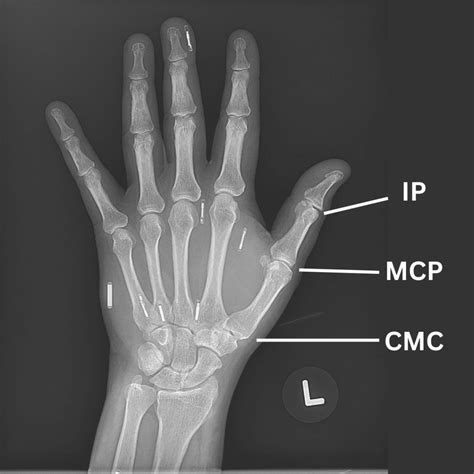

Mcp joint pain can arise from various conditions, including arthritis, injuries, and overuse. The metacarpophalangeal joints are the joints where the metacarpal bones of the hand meet the phalanges of the fingers. These joints are essential for performing daily activities such as gripping, pinching, and manipulating objects. When these joints become painful, it can significantly impact an individual's ability to perform everyday tasks.

• Imaging Tests: X-rays, MRI, or CT scans may be ordered to visualize the joints and identify any abnormalities.